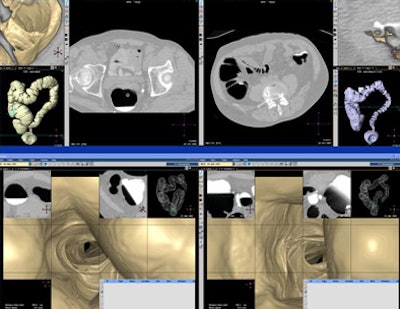

![]() |

| Results show sensitivity and specificity differences in primary reading of uncleansed 2D data (red) versus primary reading of cleansed 3D data (green). Top chart (above) shows per-polyp sensitivity differences in 90 lesions ≥ 6 mm; middle chart (below) shows per-polyp sensitivity in 53 lesions ≥ 10 mm; bottom chart shows specificity for novices and experts in both polyp size ranges. Novices demonstrated greater variability and lower overall performance compared to experts. |